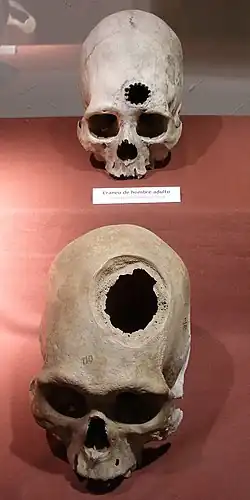

Trepanation, similar to some techniques used today, is the oldest surgical procedure known and was practised in the Stone Age in many parts of the world,[3] and in some areas may have been quite widespread. The main pieces of archaeological evidence are in the forms of cave paintings and human remains. One third of 120 skulls found at a site in France dating to 6500 BCE had undergone trepanning.[4] It was also practised widely in the pre-Columbian Andes.[5][6] These procedures were mostly performed on combatants, with evidence from skeletal remains revealing that the earliest methods usually resulted in death.[6] However, by the 1400s, Incas proved to be "skilled surgeons", as survival rates rose to about 90%, infection rates following the procedure were low and evidence was found showing that some individuals survived the surgery on multiple occasions.[6] Incan surgeons learned to avoid areas of the head that would cause injury, using a scraping method on the skull that would cause less trauma.[6] They also likely used medicinal herbs of the time, such as coca and alcohol for pain while balsam and saponin would be employed for antibiotic purposes.[6]